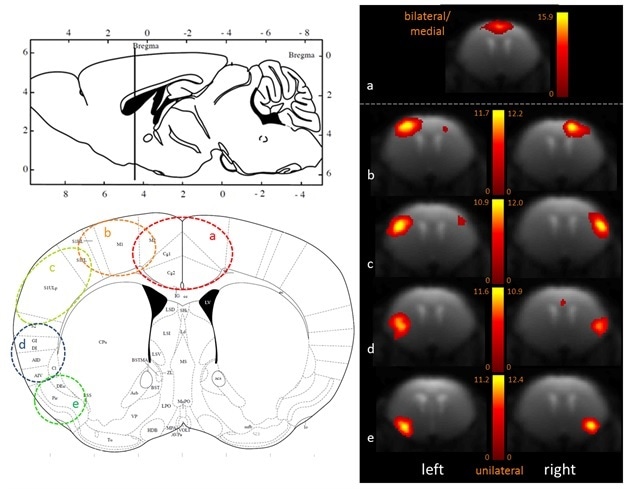

100-ICASSO also showed the segregation of functional cortical, dividing this brain area into anatomically meaningful areas as shown in Figure 2 - a) cingulate cortex, b) motor cortex, c) primary somatosensory cortex, d) insular cortex, e) piriform cortex). When performing research in animal models of brain disorders, this refinement with 100-ICASSO could be of major value for showing the functional abnormalities at particular cortical locations.

Fine-grained segregation of the cortical mouse brain functional connectivity revealed with 100-ICASSO. Bi- (a) and uni-lateral left and right ICs (b–e), matching well defined anatomical areas (see he atlas axial image - Paxinos and Franklin, 2001) are displayed.

Figure 2. Fine-grained segregation of the cortical mouse brain functional connectivity revealed with 100-ICASSO. Bi- (a) and uni-lateral left and right ICs (b–e), matching well defined anatomical areas (see he atlas axial image - Paxinos and Franklin, 2001) are displayed. Image Credit: Bruker BioSpin Group